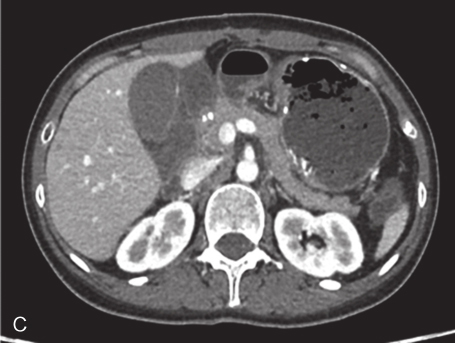

全腹部增强CT:① 胃体-胃小弯侧壁-胃窦及肝胃间区见多发软组织密度影,部分呈串珠状排列,左右径约为12cm,前后径约为4.4cm,胃窦较大者约4.5cm×3.8cm,胃窦部较大的肿物囊性变明显,胃腔阻塞;增强呈明显强化,肝左动脉、胃左动脉、胃十二指肠动脉分支参与血供;考虑为胃GIST,伴肝胃间隙转移。②肝内散在结节状稍低密度影,大者位于右后叶上段,长径1.8cm,增强呈渐进性强化;需鉴别于肝转移瘤与肝血管瘤,建议进一步行MRI增强扫描。③左侧附件区见块状软组织密度影,约3.7cm×3.1cm,增强呈轻度不均匀强化,不排除左侧卵巢肿瘤性病变。建议进一步行MRI检查。④腹腔腹膜后小淋巴结增多(图3)。

图3 2016年3月增强CT

A、B.横断位;C.冠状位

引自:胃肠间质瘤典型病例诊治与解析.第1版.ISBN:978-7-117-30146-6.主编:陶凯雄 曹 晖